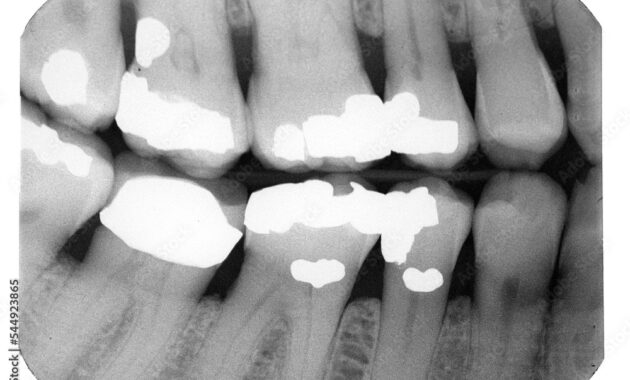

X-rays are indispensable tools in modern dentistry. They allow dentists to evaluate not only the general health of teeth but also any potential issues that may not be visible to the naked eye. Utilizing electromagnetic radiation, X-rays penetrate through soft tissues and provide a stark contrast in images where denser structures, like teeth, appear white and less dense areas, such as cavities, appear darker.

When evaluating an X-ray, each shadow, speck, and hue holds significance, creating a narrative about your dental health. Particularly concerning cavities, the X-ray will showcase these anomalies as dark spots or areas of decreased radiopacity, indicating underlying decay. Understanding these symbols equips you to better comprehend your dental health.

- Interproximal Areas: These are the surfaces between teeth. On an X-ray, cavities here can appear as dark lines or spots between adjacent teeth.

- Occlusal Surfaces: The flat tops of teeth where chewing occurs may also develop cavities. These may not always be as visible on X-rays but can appear as shallow depressions or small dark spots on the bite surfaces.

- Root Surfaces: In cases of gum recession, cavities can form on the roots of teeth. These areas will appear darker, indicating the loss of tooth structure due to decay.

Additionally, the size and extent of the cavity significantly influence its appearance on an X-ray. Small cavities may present as mere shadows, while larger ones may exhibit a more pronounced darkening, extending into the dentin beneath the enamel.

- Enamel Caries: These initial stages of cavities are often visible on X-rays as incipient lesions—slight darkening of enamel regions. The tooth structure remains intact; however, this is a clear signal for preventive measures.

- Dentin Caries: Once the decay progresses into the dentin layer, the X-ray may depict larger dark areas, clearly indicating significant tooth structure loss. These require restorative procedures.

- Pulpal Involvement: When cavities reach the pulp chamber, this is a serious condition. X-rays may show extensive darkening around the tooth’s root, suggesting infection or necrosis of the pulp, thus demanding urgent dental intervention.

- X-Ray Technique: Different techniques (periapical, bitewing, panoramic) yield unique views of cavities, with bitewing X-rays being particularly effective in visualizing interproximal decay.

- Existing Restorations: Previous fillings, crowns, or implants appear on X-rays, allowing dentists to assess their integrity and any potential underlying issues.